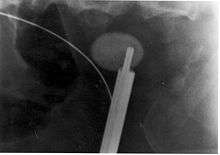

Ureteroscopic surgery

Ureteroscopy has become increasingly popular as flexible and rigid fiberoptic ureteroscopes have become smaller. One ureteroscopic technique involves the placement of a ureteral stent (a small tube extending from the bladder, up the ureter and into the kidney) to provide immediate relief of an obstructed kidney. Stent placement can be useful for saving a kidney at risk for postrenal acute renal failure due to the increased hydrostatic pressure, swelling and infection (pyelonephritis and pyonephrosis) caused by an obstructing stone. Ureteral stents vary in length from 24 to 30 cm (9.4 to 11.8 in) and most have a shape commonly referred to as a "double-J" or "double pigtail", because of the curl at both ends. They are designed to allow urine to flow past an obstruction in the ureter. They may be retained in the ureter for days to weeks as infections resolve and as stones are dissolved or fragmented by ESWL or by some other treatment. The stents dilate the ureters, which can facilitate instrumentation, and they also provide a clear landmark to aid in the visualization of the ureters and any associated stones on radiographic examinations. The presence of indwelling ureteral stents may cause minimal to moderate discomfort, frequency or urgency incontinence, and infection, which in general resolves on removal. Most ureteral stents can be removed cystoscopically during an office visit under topical anesthesia after resolution of the urolithiasis.[93]

More definitive ureteroscopic techniques for stone extraction (rather than simply bypassing the obstruction) include basket extraction and ultrasound ureterolithotripsy. Laser lithotripsy is another technique, which involves the use of a holmium:yttrium aluminium garnet (Ho:YAG) laser to fragment stones in the bladder, ureters, and kidneys.[94]